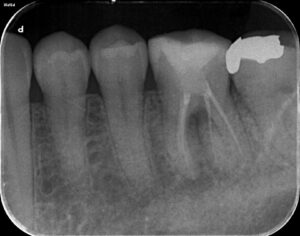

今回のケースも最小限の入り口から根管治療を行うのですが、Radix Entomolarisと呼ばれる歯根のところが難しいと予想しました。事前にCBCTを撮影して、シミュレーションを毎回行っています。あとは私が開発した方法を利用して入り口の大きさを決定しています。それが下のレントゲン写真です。